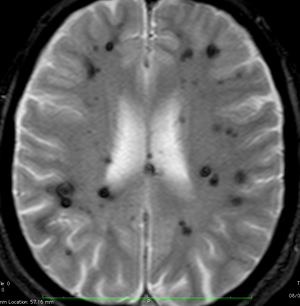

多発性海綿状血管腫 multiple cavernous hemangioma

家族性海綿状血管腫 familial cavernous hemangioma

この様な無数の海綿状血管腫を見ることがあります。多くの場合は家族性(遺伝性)の海綿状血管腫です。200個を超える海綿状血管腫があっても普通に何の障害もなく暮らしている患者さんもいます。脊髄の中にも発生しますから,脊髄のMRIもしていただきましょう。

小さな多発性の海綿状血管腫は,T2*(ティーツースター)という左の画像では見えるのですが,右にあるような普通のT1強調画像というのでははっきりみえません。